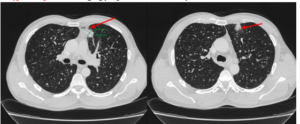

Case lâm sàng: Ứng dụng trí tuệ nhân tạo (Artificial intelligence – AI) trong chẩn đoán và điều trị sớm Ung thư phổi tại Trung tâm Y học hạt nhân và Ung bướu, Bệnh viện Bạch Mai

Case lâm sàng: Ứng dụng trí tuệ nhân tạo (Artificial intelligence – AI) trong chẩn đoán và điều trị sớm Ung thư phổi tại Trung tâm Y học hạt nhân và Ung bướu, Bệnh viện Bạch Mai GS.TS. Mai Trọng Khoa, PGS.TS. Phạm Cẩm Phương, BSNT Nguyễn Ngọc Ánh...